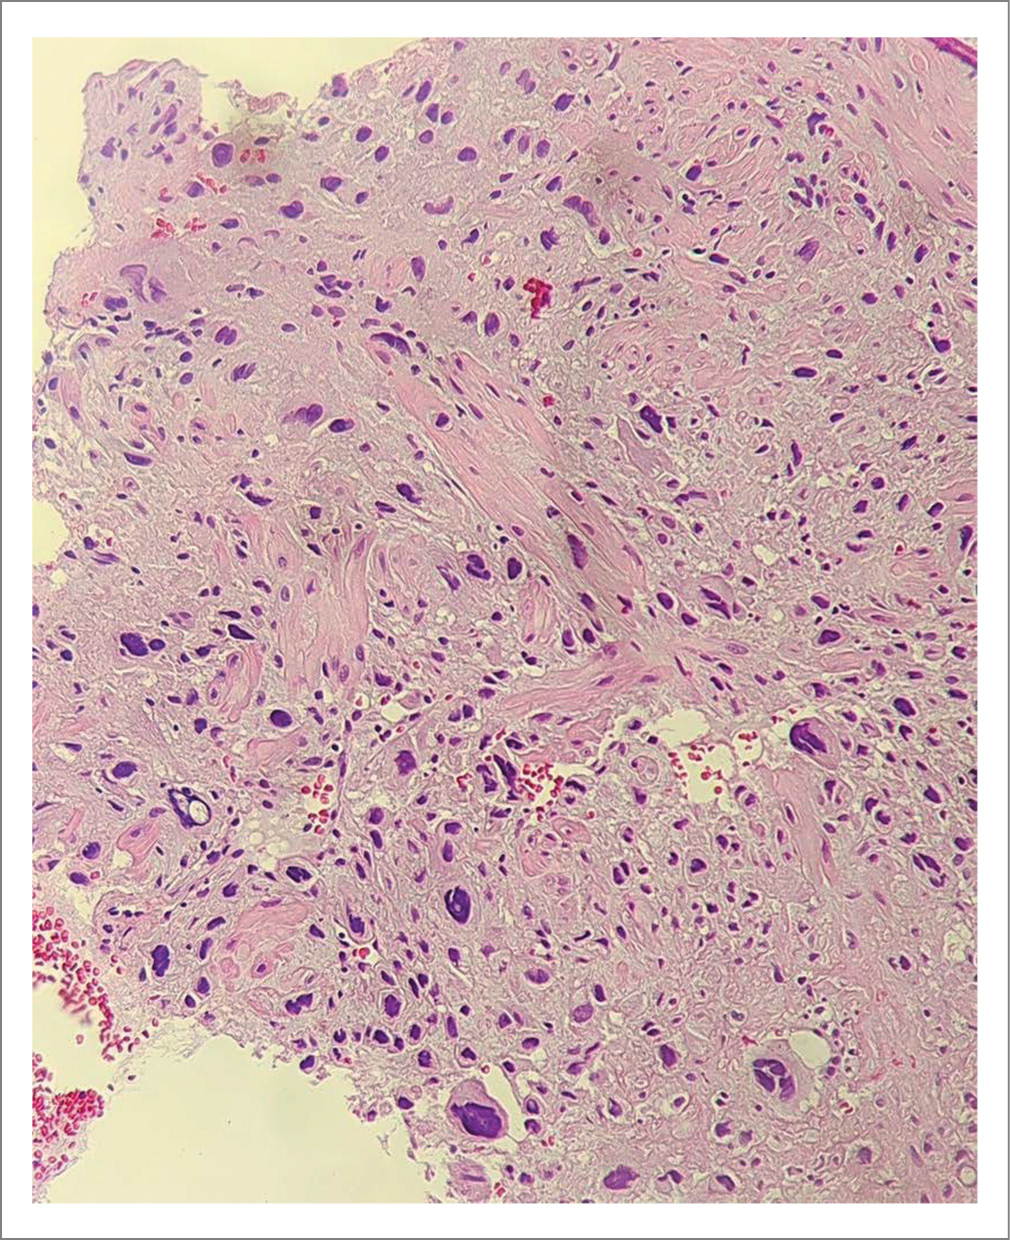

- Свертки крови, представленные частично лизированными и неизмененными эритроцитами, эндометрий без четких признаков стадии менструального цикла, с признаками очаговых гиперпластических изменений, без атипии. На этом фоне обнаружены крупные фрагменты эндометрия с ростом полиповидной опухолеподобной ткани, инфильтрирующей прилежащие части миометрия, построенной из крупных многогранных, преимущественно мононуклеарных, клеток, а также многочисленных сливающихся пластов клеток трофобласта с гигантскими гиперхромными ядрами с резко выраженным полиморфизмом. В пределах доставленного материала фокусов некрозов достоверно не обнаружено, признаков лимфоваскулярной инвазии также не выявлено (рис. 1, 2).

Рис. 1. Клетки трофобласта с крупными гиперхромными ядрами, «раздвигающие» мышечные волокна миометрия. Окраска гематоксилин-эозином. ×20.

Fig. 1. Trophoblast cells with large hyperchromic nuclei, separating muscle fibers of the myometrium. Hematoxylin and eosin staining. ×20.